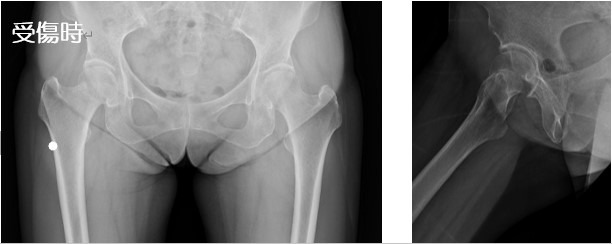

2020-07-21 手外科・外傷 ページ内リンク 髄内釘(short femoral nail) Sliding hip screw 大腿骨頚部骨折(骨接合術) 大腿骨頚部骨折(人工骨頭挿入術) 腿骨転子部骨折(髄内釘) 髄内釘(short femoral nail) Sliding hip screw 大腿骨頚部骨折(骨接合術) 大腿骨頚部骨折(人工骨頭挿入術) 腿骨転子部骨折(髄内釘) 関連ページ 手外科・外傷 一覧へ戻る